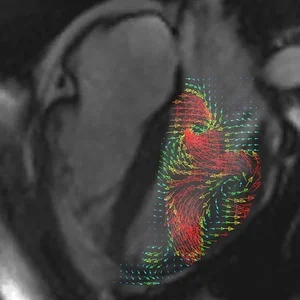

Welcome to the Gharib Research Group! We are a team of researchers, engineers, and students addressing a vast array of problems spanning the fluid dynamics of wind and sea, bio-inspired systems, biomedical and health applications, robotic flight, imaging, and art–science domains.

Research Highlights: